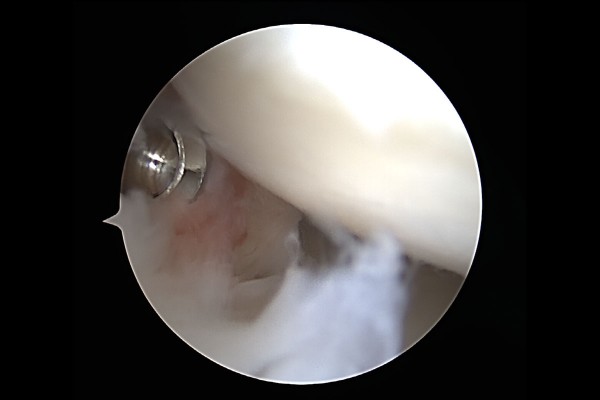

30ec6ec96c3e395fd52bc2174c5bac54_1768985224_7985.jpg

수술기구를 이용하여 석회에 창을 내고,

30ec6ec96c3e395fd52bc2174c5bac54_1768985239_1099.jpg

치약 짜듯이 쥐어 짜게 되면 하얀 석회가루가 나오게 됩니다.

30ec6ec96c3e395fd52bc2174c5bac54_1768985252_1451.jpg

추가로 빨간 염증도 제거해줍니다.